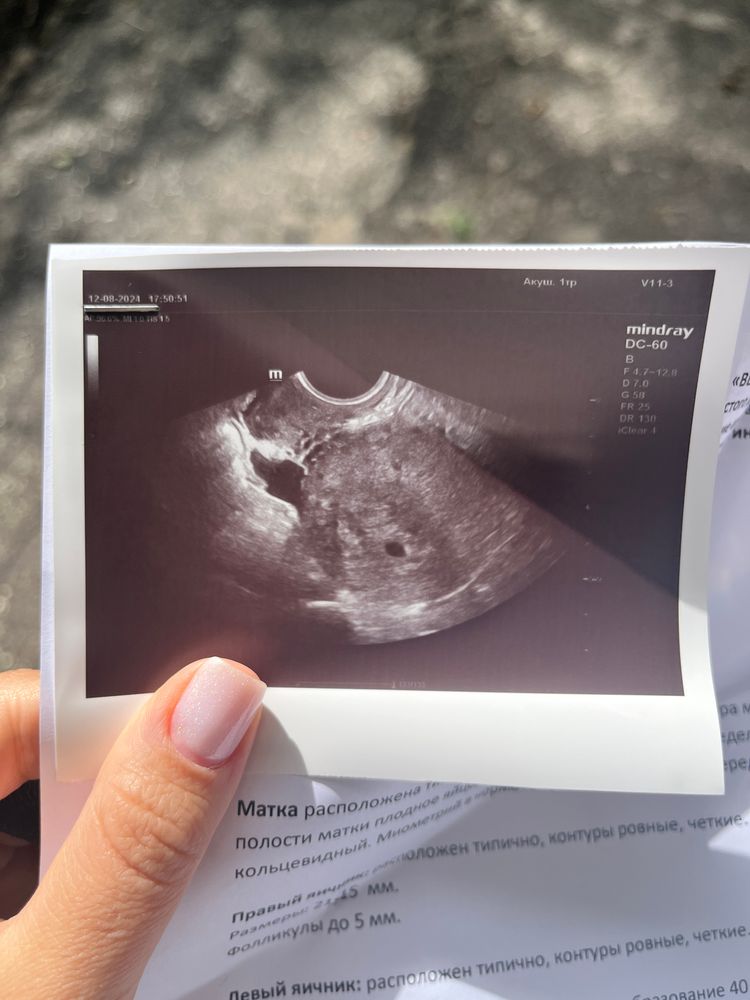

Экстренно была на узи🙂

12.08.2024